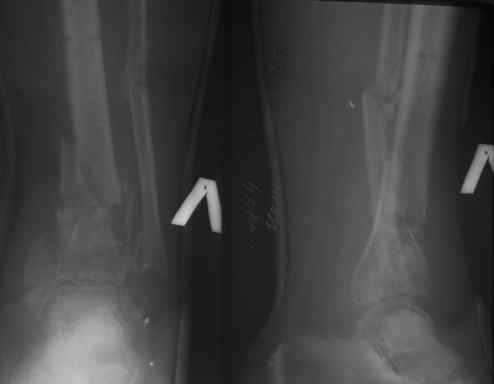

Предоставлены снимки голени на сегодня(см. сообщение выше).

Начать нужно с того, что аппарат больной сняли чуть более месяца назад, в приложении Рг перед снятием.

Больная проносила его 6 месяцев. Все чего мы смогли добиться- сохранить отломки в куче, приблизительно напоминающей вилку голеностопного сустава. Надо будет постараться убедить ее проносить его еще сколько-нибудь. Патологическая подвижность в области н/3 голени есть. Если предположить, что мы добьемся артродезеа, не факт, что перелом срастется. Стопа в эквинусе 120гр.

Такую, что вместо выведения из эквинуса можно получить введение в рекурвацию. Плотность кучки осколков дистального отломка оставляет желать лучшего. Это хорошо видно на последнем синмке в АВФ(см. выше), где произошла резорбция вокруг стержня во внутренней лодыжке и фактически его миграция из кости.